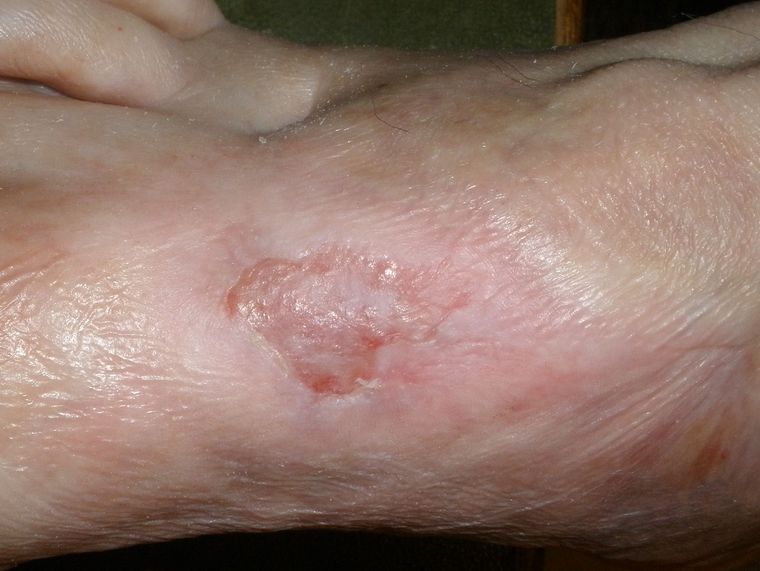

Es geht nur langsam voran, Foto 15.11.08: